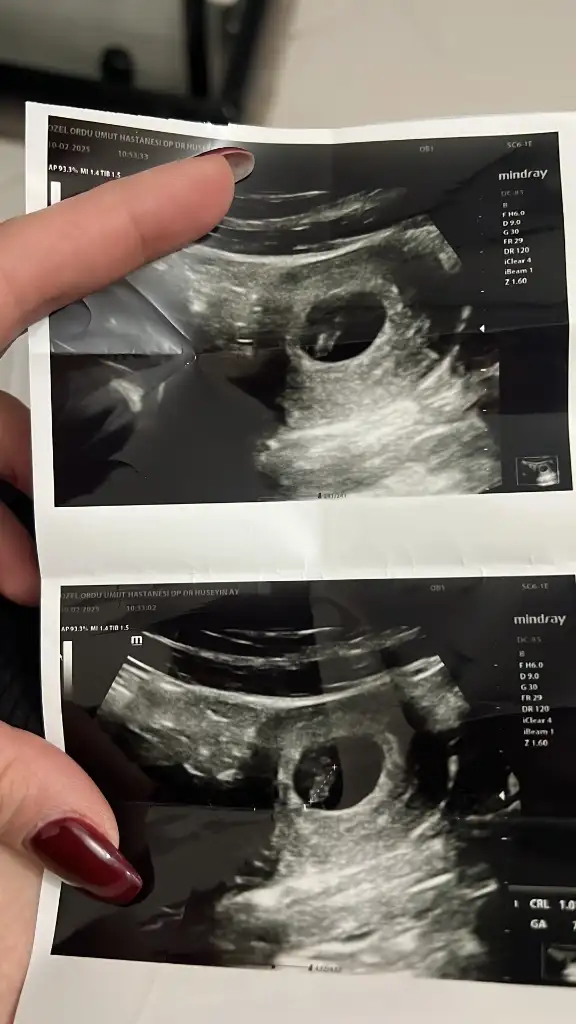

Ramzi teorisi okudum yüzde 97 dogruymuş.Ama neye göre bakcam ultrasona bilemedim. Size sormak istedim Bebeğim sağa daha yakın sanki bası da solda ayakları sağa bakıyor yani. Anlamadım ben. Sağlıklı olsun tabi kız erkek fark etmez ama merak ettim. İlk foto 5+5 iken 2.foto 9+3ken

Kız bebek canımBir tahminde ben alabilir miyim7 haftalık karın ultrason

Benim icinde tahminde bulunabilir misiniz 7 haftalık karından ultrosonEger sol alttaki golge bebek ise kiz bence

Bende tahmin alabilir miyim 7 haftalık karından ultroson11 haftalık resimde kız bebek gibi canım